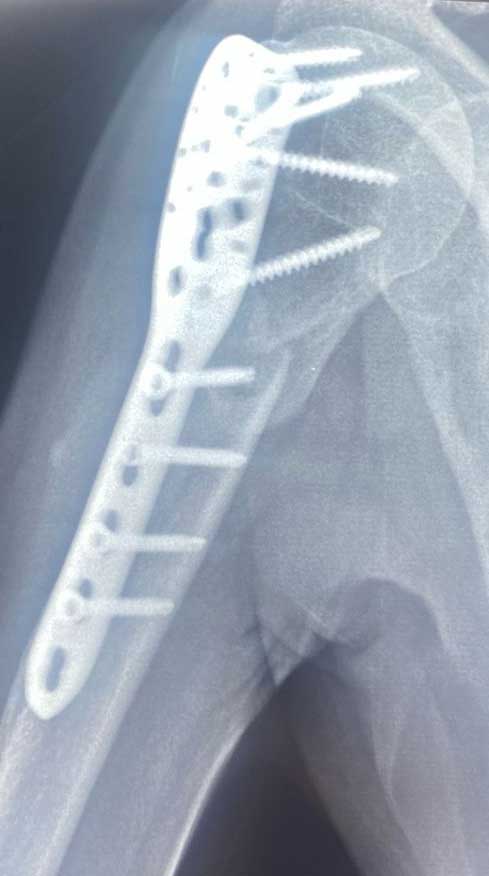

Fractura

de hombro

Pérdida de la continuidad del tejido óseo de la articulación del hombro, articulación acromioclavicular o cintura escapular, las cuales están constituidas por humero, escápula y clavícula.

¿Por qué se realiza?

El tratamiento puede ser quirúrgico o conservador (no quirúrgico) el cual estará determinado por las características del paciente, el hueso fracturado y el desplazamiento de los fragmentos, el cual puede consistir en inmobilizaciones o cirugías abiertas, mínima invasivas ó artroscopicas.

Cuidados después de la intervención

Es necesario cuidar la osteosíntesis del hombro por semanas después de la cirugía, apegado a la terapia física frecuente para evitar el dolor del edema y rigidez postquirúrgica. Los protocolos para la rehabilitación del hombro quirúrgico están muy bien protocolizados y estandarizados para mejorar el resultado y varían de 4-12 semanas.

Resultados esperados

En cuanto a fracturas de hombro es decir del humero proximal, escápula o articulación glenohumeral es importante siempre tener en cuenta el grado de la lesión, es decir, la complejidad del numero de estructuras óseas y si afecta o no la articulación, y si es una fractura con múltiples fragmentos. Pero la intención de una cirugía es siempre conseguir el mejor resultado funcional para mejorar la calidad de vida del paciente.